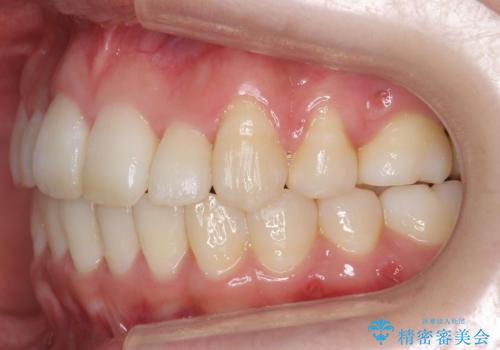

前歯は重度のがたつき、また奥歯はすれ違っていました。

治療は3年以上かかりそうと説明しましたが、2年台で終わらせることができました。

上下左右4本抜歯の可能性を説明していましたが、実際は上顎2本の小臼歯抜歯で済みました。

上下の顎の幅もあっておらず、成人でしたが手術なしで上あごを骨から広げる処置(急速拡大装置)を行いました。